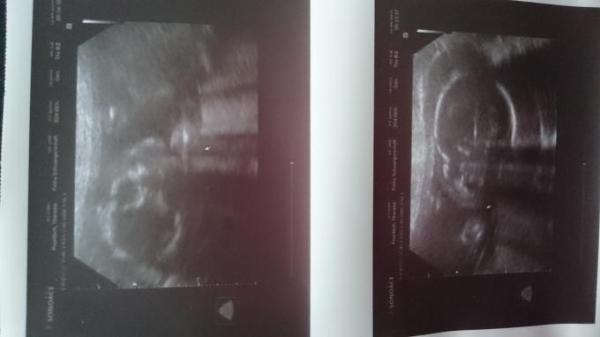

Wir haben ein gesundes und agiles Baby. Es mag zwar noch immer keinen Ultraschall, aber es hat ganz brav seine Organe anschauen lassen. Rücken ist zu, Herzchen schlägt kräftig und sieht gut aus und das Gehirn war auch schön symmetrisch zu erkennen. Es ist ca 25 cm groß und etwa 430g schwer. Die Ärztin meinte ein Mädchen erkennen zu können. Wir konnten, trotz der genauen Beschreibung, als Laien nicht so viel erkennen. Da bei uns der Praxiskollege die Feindiagnostik machen darf, haben wir in zwei Wochen einen Termin bei ihm und sind gespannt, ob es sich bestätigt oder ändert. Heute haben wir mal Köpfchen und Gesicht als Bild bekommen. :-)

Bild zu 2. Screening - Forum für August - Mamis